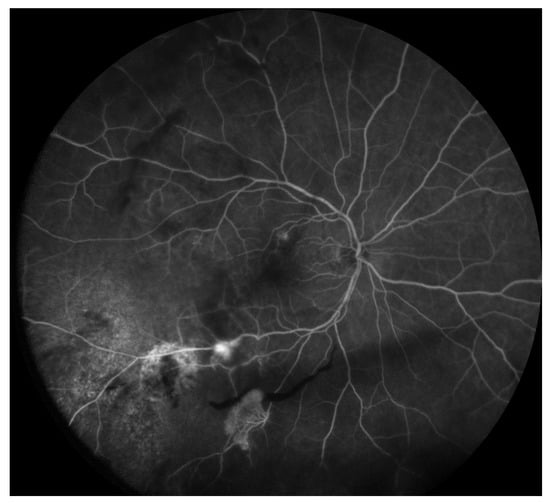

3.3. Radiation Optic Neuropathy